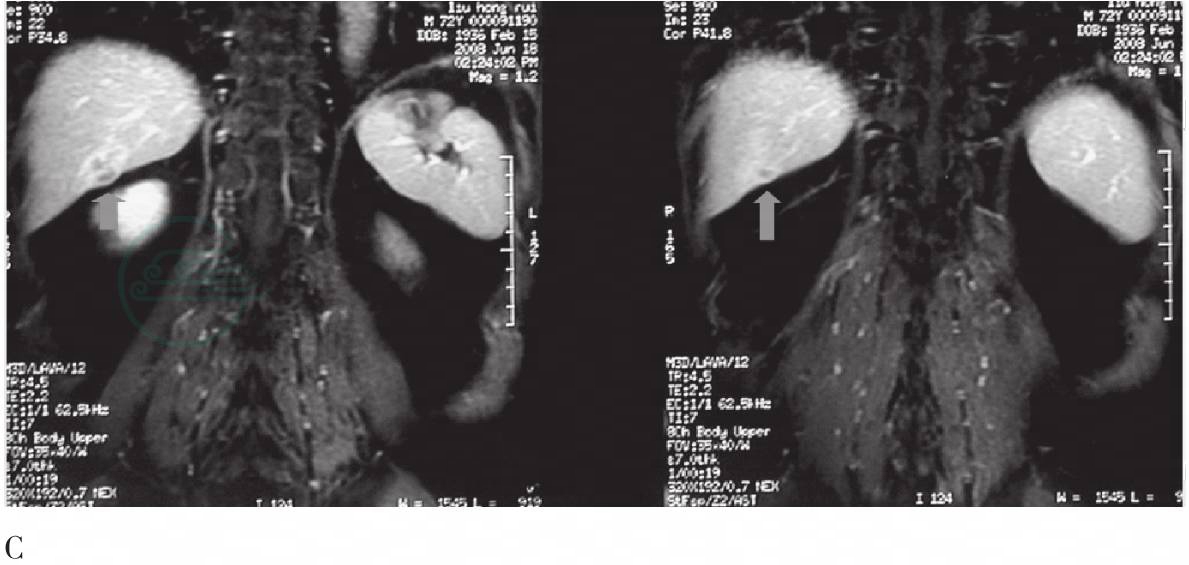

增强MRI示肝右叶1.5cm×2.0cm低信号区,周边见环形强化,病灶内似见隧道(图2)。

图2 MR增强腹部横断及冠状层图

A. MR增强扫描血流期,显示肝右叶后下缘不规则、信号不均匀结节,周围呈环状强化;B、C. MR增强扫面血池期横断面和冠状面,显示结节病灶周围环状强化更加明显,内见隧道样改变